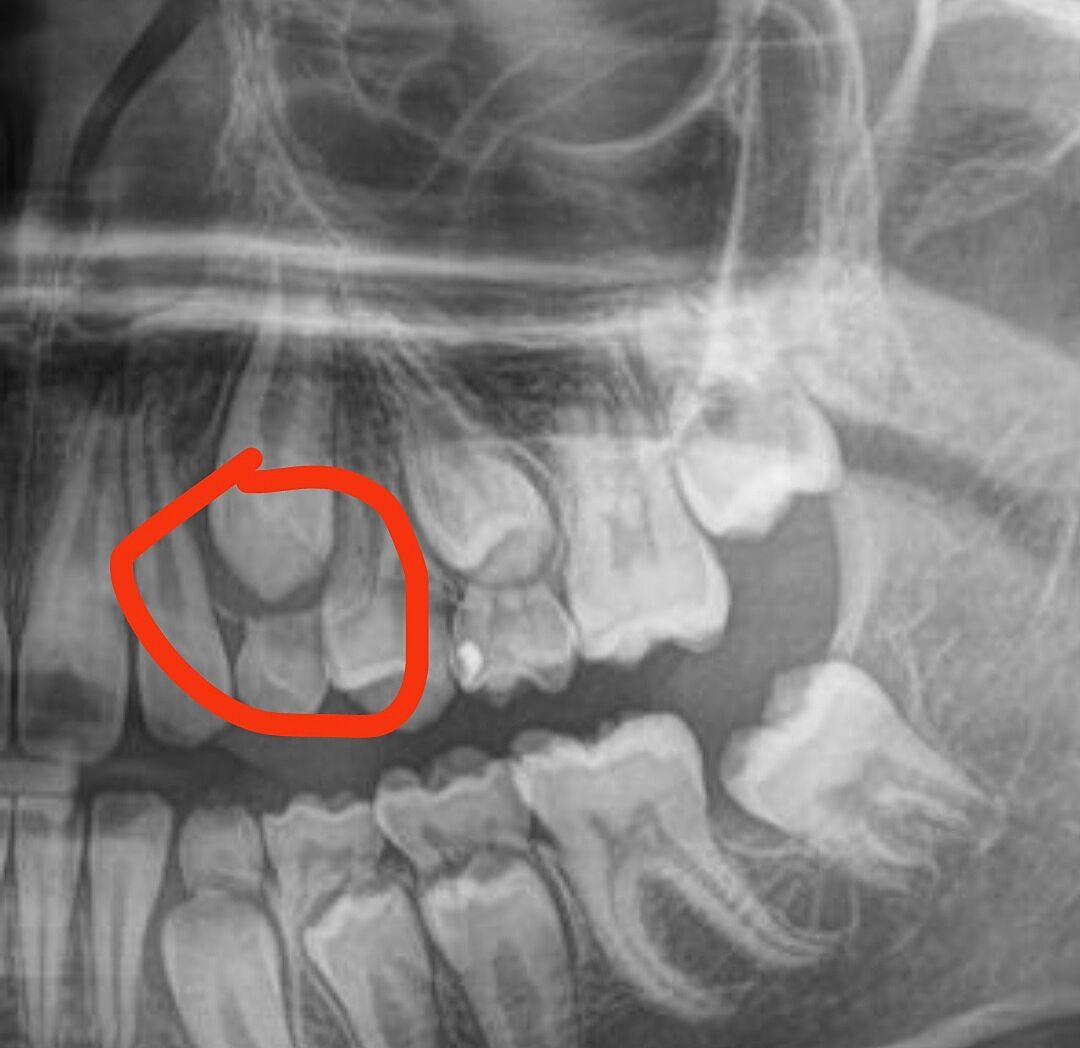

Такий знімок. Видно добре постійні, а молочні не хитаються.

Звичайно, я слухатиму лікаря! Але хочеться і досвід чужий послухати. 🤗 Чи це на знімку вважається, що зуб дуже близько і може вирости збоку?

У мого теж були такі зуби. Але у автора на знімку видно що нічого в бік не росте, корені молочних зубів розчинилися , постійні їх витісняють анатомічно правильно.

Ви бачите, що розчинились, так? Бо я не дуже розумію як вони б мали виглядати. Значить рвати буде не дуже боляче, надіюсь.

Видно що між зубами темний простір пустий .

Він випав вже. Зверху лишився 3 і 5. Знизу 3,4,5 молочні

Зрозуміло. Знизу такого нема. Там значит важче буде